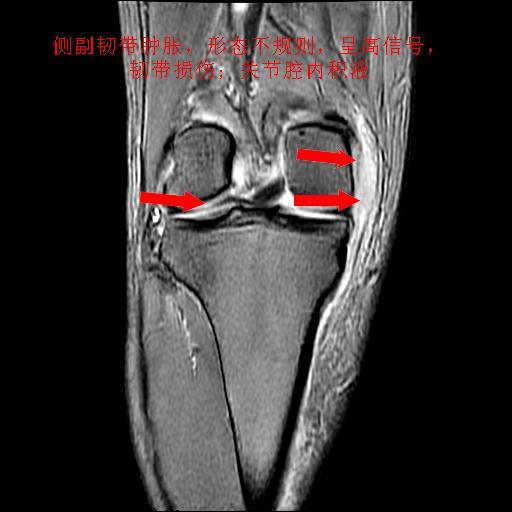

40岁男性,右膝关节外伤,x光平片示,髁间隆突撕脱骨折。

1、前交叉韧带撕裂;

2、外侧半月板后角撕裂;

3、关节腔积液。

髁间隆突撕脱骨折;内侧副韧带损伤。

1、内侧副韧带撕裂;

2、前交叉韧带撕裂;

3、滑膜炎伴关节腔积液。

1、前交叉韧、内侧副韧带撕裂;

3、关节腔积液。4、髁间脊撕脱骨折。